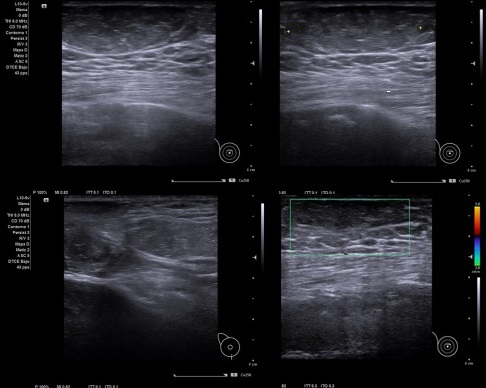

Caso 2: Hombre de 91 años, con bulto sobre el pezón que se desplaza perfectamente y se puede coger con los dedos, de meses de evolución.

Caso 2: Se aprecia exoestructura compatible con lipoma… No captación Doppler. Bien delimitado, de unos 20 mm de diámetro mayor.

Caso 2: Lipoma en piel de mama.

Diagnóstico diferencial: Masa de origen mamario.